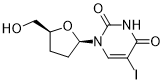

馬鞍山致研生物醫(yī)藥科技有限公司成立于馬鞍山市鄭浦港新區(qū)現(xiàn)代產(chǎn)業(yè)園。公司專(zhuān)注于生物小分子、醫(yī)藥中間體相關(guān)產(chǎn)品的研發(fā)和生產(chǎn),產(chǎn)品主要包括DNA亞磷酰胺單體、RNA亞磷酰胺單體、特殊單體以及按照客戶(hù)要求定制的RNA和DNA,并且公司提供定制合成等方面的研究服...

馬鞍山致研生物醫(yī)藥科技有限公司成立于馬鞍山市鄭浦港新區(qū)現(xiàn)代產(chǎn)業(yè)園。公司專(zhuān)注于生物小分子、醫(yī)藥中間體相關(guān)產(chǎn)品的研發(fā)和生產(chǎn),產(chǎn)品主要包括DNA亞磷酰胺單體、RNA亞磷酰胺單體、特殊單體以及按照客戶(hù)要求定制的RNA和DNA,并且公司提供定制合成等方面的研究服...